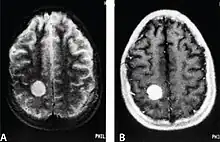

CNS metastases are diagnosed through imaging techniques that produce detailed images of the inside of the body, including parts such as the bones, organs, muscles, and nerves.[13] Magnetic resonance imaging (MRI) and computed tomography (CT) are two representative imaging procedures for this purpose.[12]

MRI scans use strong magnetic fields and radio waves to create an image, while CT scans use X-rays. MRI scans produce more detailed images of bodily structures, particularly soft tissues including the brain,[13] and are better at detecting CNS metastases than CT scans. However, CT scans are sometimes used for the initial imaging modality due to their lower cost and efficiency in screening for multiple conditions.[14]